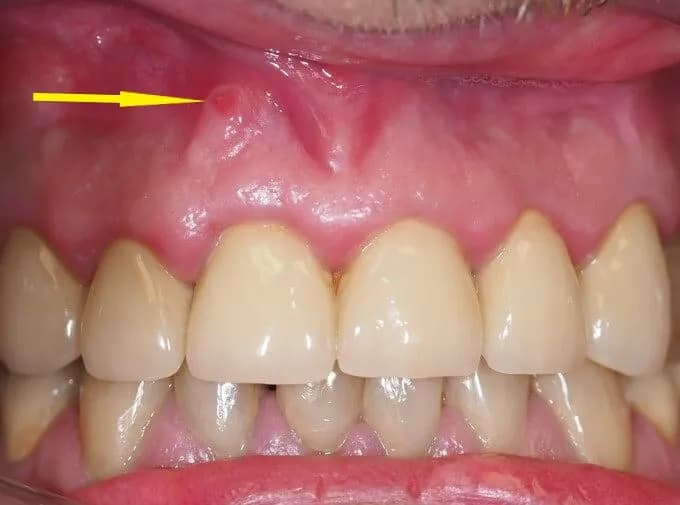

Ropień na dziąśle to bolesna i nieprzyjemna zmiana, która zazwyczaj ma postać zaczerwienionego, wypukłego bąbla. Może być wypełniona gęstą, żółtawą lub zielonkawą wydzieliną, znaną jako ropa. Występuje najczęściej w miejscu styku zęba z dziąsłem lub na jego powierzchni. W początkowej fazie ropień może towarzyszyć uczucie bolesnego rozpierania, które często promieniuje na szczękę, co może być niezwykle uciążliwe.

Aby rozpoznać ropień na dziąśle, należy zwrócić uwagę na kilka kluczowych cech wizualnych. Zwykle ropień ma postać wypukłej zmiany, która jest zaczerwieniona i może przypominać mały bąbel lub krostkę. Wewnątrz zmiany znajduje się gęsta, żółtawa lub zielonkawa wydzielina, co jest charakterystyczne dla obecności ropy. Ropień może występować w okolicy styku zęba z dziąsłem lub wyżej na dziąśle, co może wskazywać na jego lokalizację oraz potencjalne źródło infekcji.